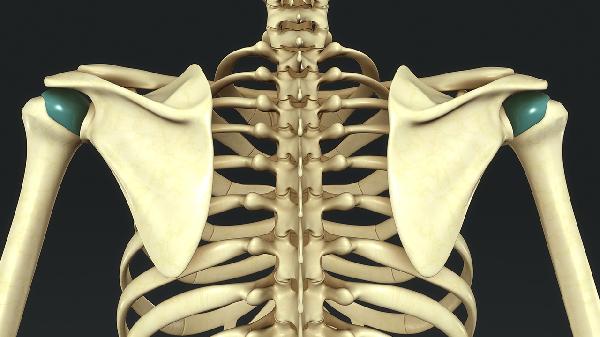

2.發(fā)病原因不同:肩周炎是指肩關(guān)節(jié)周圍軟組織的慢性無(wú)菌性炎癥,肩關(guān)節(jié)急性扭傷、軟組織勞損或退變、上肢固定過(guò)久等為該病病因;胸廓出口綜合征是指鎖骨下動(dòng)、靜脈及臂叢神經(jīng)在胸廓上口受壓而產(chǎn)生的一系列癥狀,其病因有第7頸椎橫突過(guò)長(zhǎng)、第1肋骨上移、斜角肌異常等。

3.癥狀不同:肩周炎常見癥狀為肩痛,呈持續(xù)性,氣候變化和勞累可使疼痛加重,并放射至頸項(xiàng)和上肢,但放射痛與神經(jīng)分布不一致?;颊哌€可出現(xiàn)肩關(guān)節(jié)僵硬及活動(dòng)受限,嚴(yán)重時(shí)肩部肌肉出現(xiàn)萎縮;胸廓出口綜合征可分為臂叢神經(jīng)受壓和血管受壓,當(dāng)臂叢神經(jīng)受壓時(shí),主要表現(xiàn)為患肢肩部及上肢疼痛、無(wú)力,病變?cè)缙谔弁闯书g歇性,并向前臂及手部尺側(cè)放射,嚴(yán)重時(shí)前臂及手部尺側(cè)可出現(xiàn)感覺異常,表現(xiàn)為指力減弱、精細(xì)活動(dòng)不靈活、小魚肌及骨間肌出現(xiàn)萎縮,表現(xiàn)為“爪形手”。血管受壓時(shí),患側(cè)上肢可出現(xiàn)套狀樣感覺異常,表現(xiàn)為肢體發(fā)涼怕冷、軟弱無(wú)力、顏色蒼白、遠(yuǎn)端水腫等。